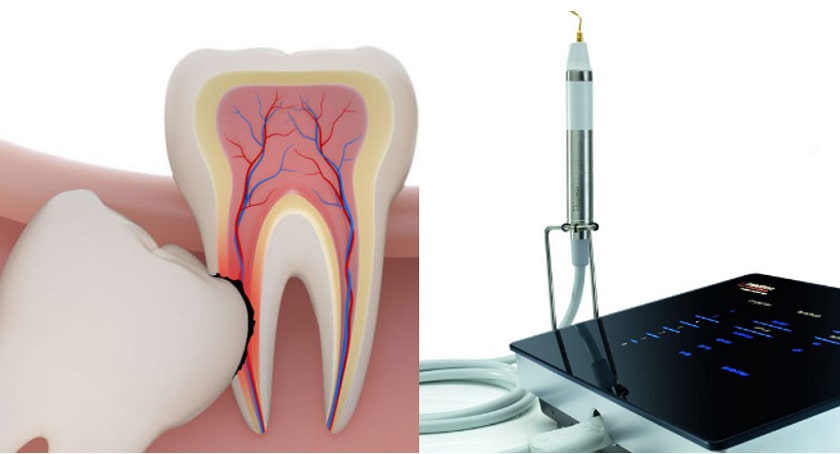

Nhổ răng khôn bằng máy siêu âm Piezotome là phương pháp hiện đại sử dụng bước sóng siêu âm để nhổ răng siêu âm để dùng sóng siêu âm phá vỡ các dây chằng xung quanh răng, khiến răng dễ dàng được lấy ra mà không cần phải tách lợi. Đây được xem là bước tiến vượt bậc của nha khoa hiện đại giúp quá trình phẫu thuật diễn ra nhanh chóng, an toàn và nhanh lành thương

1 Nhổ răng khôn bằng máy siêu âm Piezotome là gì?

Máy siêu âm Piezotome là sự kết hợp hoàn hảo giữa chế độ Piezotome, Newtron và màn hình cảm ứng, tích hợp nhiều chế độ để sử dụng cho phẫu thuật xương chuyên sâu, tạo hình xương, mở xương, nâng xoang, nhổ răng và điều trị nha chu, nội nha.

Máy Piezotome được điều khiển bằng chân và được kích hoạt theo từng bước năng lượng giúp bác sĩ điều chỉnh chính xác mức năng lượng sóng siêu âm trong quá trình phẫu thuật, từ đó rút ngắn thời gian thực tế đồng thời giúp bệnh nhân giảm sưng tấy, giảm đau và săn chắc hàm sau 24 tiếng phẫu thuật.

Hình ảnh máy nhổ răng siêu âm Piezotome

Hiểu một cách đơn giản, máy Piezotome sử dụng năng lượng rung siêu âm ở tần số cao để loại bỏ răng thay vì sử dụng lực ma sát do chuyển động xoay của mũi khoan. Chính vì vậy, khi sử dụng máy Piezotome sẽ tránh làm tổn thương các cấu trúc mô mềm và giảm chảy máu khi phẫu thuật.

Nguyên lý hoạt động của máy Piezotome là sử dụng các đầu mũi khoan chuyên dụng, có kích thước chỉ từ 0,2 – 0,5mm rung liên tục theo sóng siêu âm với biên độ và tần số khác nhau. Ngoài ra, máy siêu âm Piezotome còn tích hợp thêm hệ thống bơm nhu tự động trong tay cầm, có tác dụng phun nước để làm mát các đầu cắt giúp chúng không bao giờ bị quá nóng và hạn chế tối đa nguy cơ hoại tử tế bào xương khi phẫu thuật.